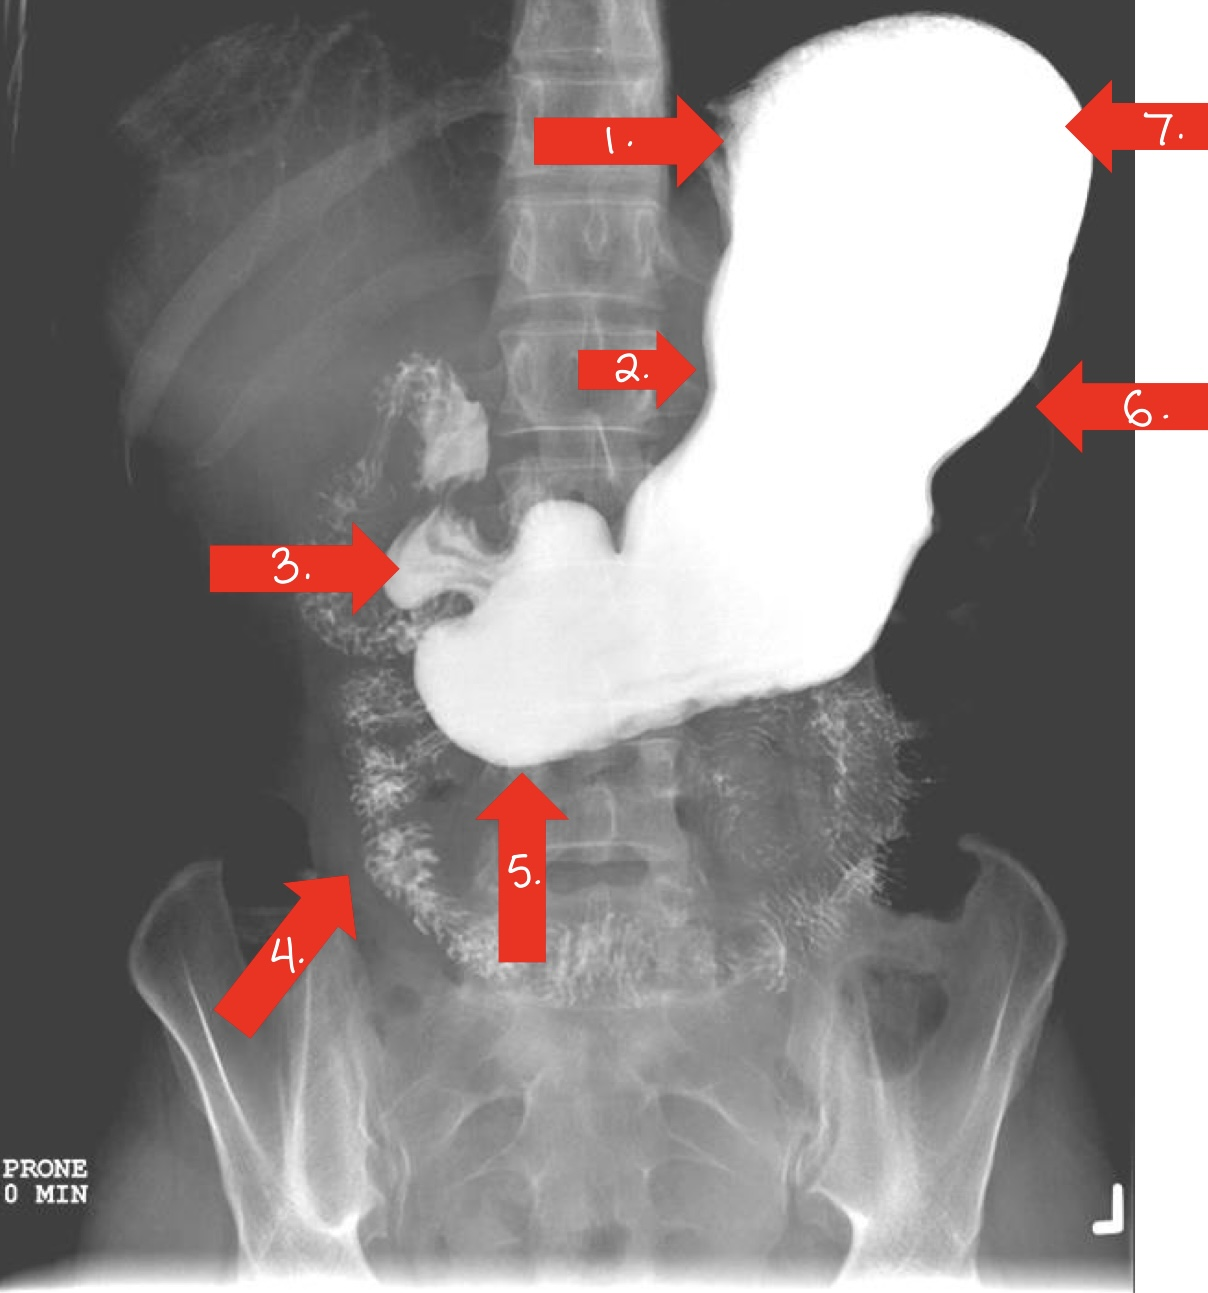

What is 1

fundus/stomach

What is 2

duodenal bulb/small intestine

What is 3

pylorus

or pyloric antrum

What is 4

ileum/small intestine

What is 5

jejunum/small intestine